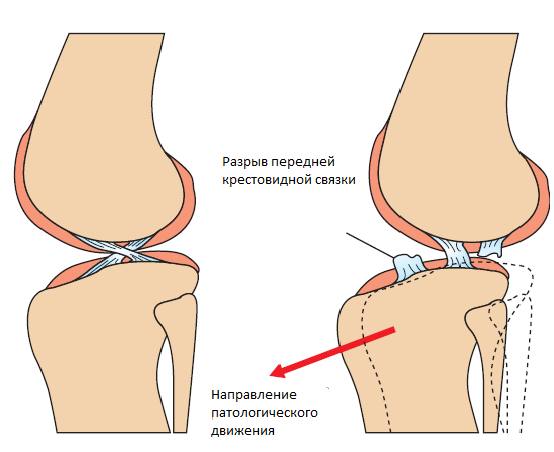

Но для начала краткий экскурс в то, что же происходит в суставе: при разрыве передней крестовидной связки естественным образом нарушается ее функция, которая состоит в том, чтобы не давать смещаться большеберцовой кости вперед и ограничивать вращение большеберцовой кости вовнутрь. Как следствие бедренная кость как бы «сползает» назад при сгибании лапы и тем самым травмирует медиальный мениск, растягивает капсулу сустава, повреждает суставные поверхности, вызывая воспаление и, впоследствии – артроз